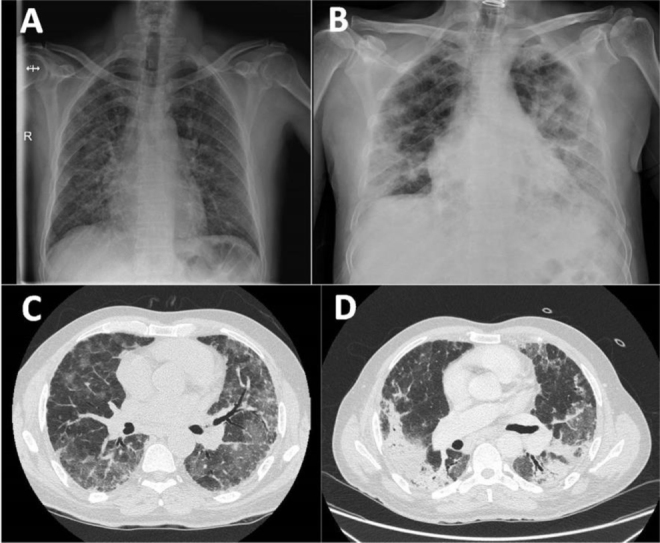

Bilateral Organizing Pneumonia Secondary to Rhinovirus Infection in a Patient With a Solid Organ Transplant